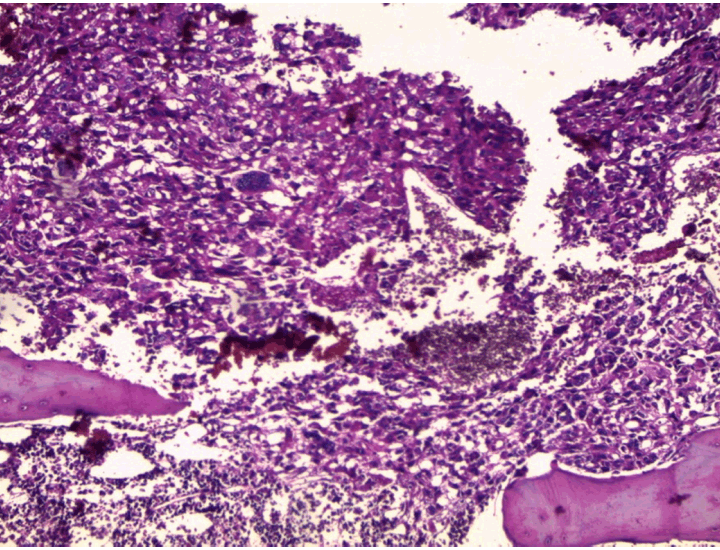

At the pathology laboratory, we received a piece of the left lower limb amputation. (Figure 2) We opened it. Gross examination of the resected distal femur revealed a 22x5 cm intramedullary multicystic hemorrhagic destructive tumor with cortical destruction and extension into the adjacent anterior and posterior soft tissues. The latter component of the mass was larger than the intraosseous tumor. (Figure 3) The articular surface was not involved. We cut the femur in its longest axis with electric saw. (Figure 4) Fixation in 10% neutral buffered formalin for 48 hours and decalcification of bone with nitric acid were performed. Slice of bone section was included in full. Many specimens from soft tissues and the surgical margins were also taken. Microscopic view of histological specimens of tumor stained with hematoxylin andeosin showed prominent blood filled cysts with malignant stroma in septa separating cysts. (Figure 5) (Figure 6) It contained atypical tumor cells oval or round of variable size with osteoblast-like multinucleated giant cells and a variable amount of immature osteoid. (Figure 7) (Figure 8) (Figure 9) (Figure 10) (Figure 11) (Figure 12) Numerous mitotic figures were noted (Figure 13). The tumor was located at 6 cm from the bone limit and 2 cm at the edge of the soft tissues. The resection margins were negative. The marrow, scooped and submitted separately, was negative.

Figure 5: Low magnification showing large blood-filled cystic spaces with septa composed of loose hemorrhagic tissue with sarcomatous cells (H&E stain, x400).

Figure 6: Medium-power magnification shows cystic spaces without lining surrounded by septa containing highly atypical malignant cells (H&E stain, x100).

Figure 7: Medium-power view of hemorrhagic area with floating, noncohesive tumor cells, infiltrating trabecular bone (H&E, stain, x100).

Microscopic findings revealed highly pleomorphic cells and foci of bone matrix formation between blood filled cyst like spaces, confirming the diagnosis of telangiectatic osteosarcoma. In some cases, where septa have broken down, atypical stromal cells may be identified, free-floating within the blood clot.[4] The amount of osteoid varies, but usually fine and lacelike osteoid is observed in minimal amount. [1] [4][6] However, this feature is not essential to establish the diagnosis of telangiectatic osteosarcoma. [4]